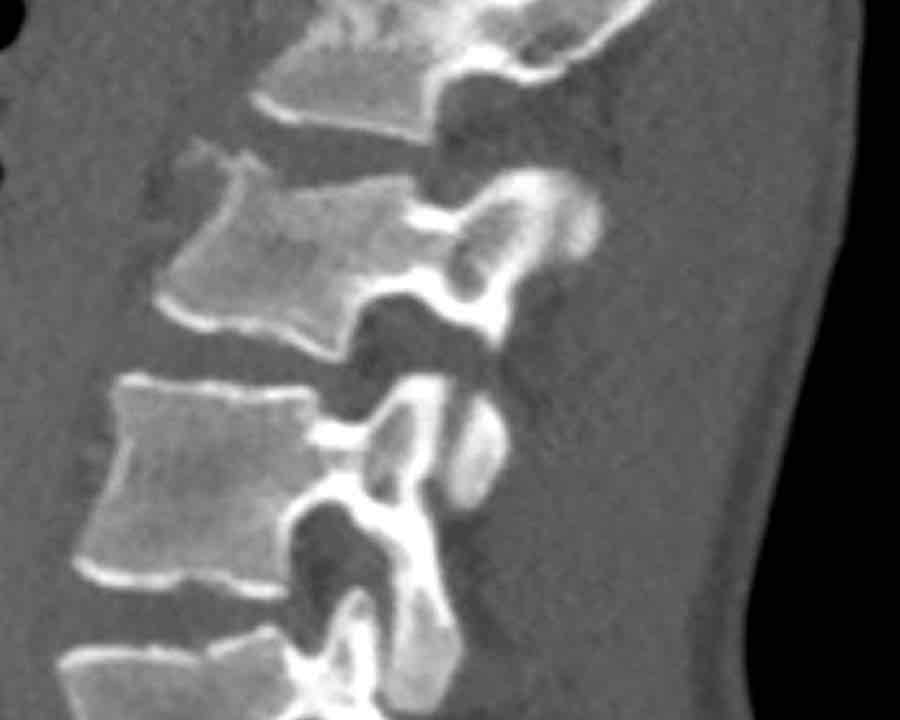

Findings:

- No C or B injury

- Fractures vertebral body with involvement of upper endplate (1 point) and posterior wall (2 points)

Conclusion

Injury type A3